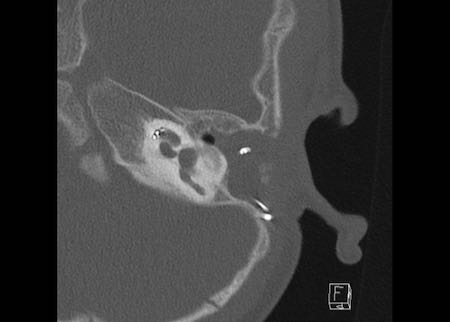

Ca lâm sàng 2

Các hình ảnh này cho thấy một điện cực cấy ghép bị lạc chỗ.

Điện cực ốc tai được đưa vào phía dưới vòng đáy của ốc tai và kết thúc ở vùng hạch gối (geniculate ganglion).